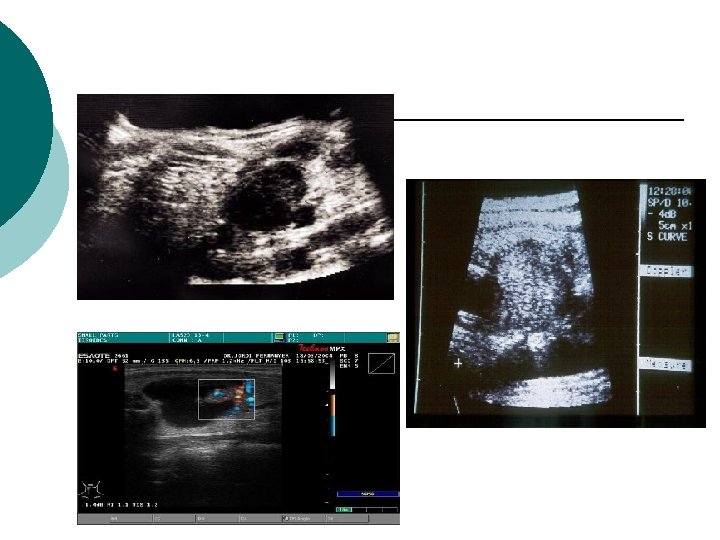

¡ 2. - ECO: VOLUMEN ¡ MULTICENTRICIDAD ¡ SOLIDO-QUISTICO ¡ GUÍA LA PAAF ¡ l !!!NO DIFERENCIA BENIGNO DE MALIGNO!!! ¡ Sospechar malignidad cuando: l l l Halo alrededor incompleto Hipoecogenicidad Microcalcificaciones Márgenes irregulares Incremento de vascularización Invasion y linfadenopatías regionales